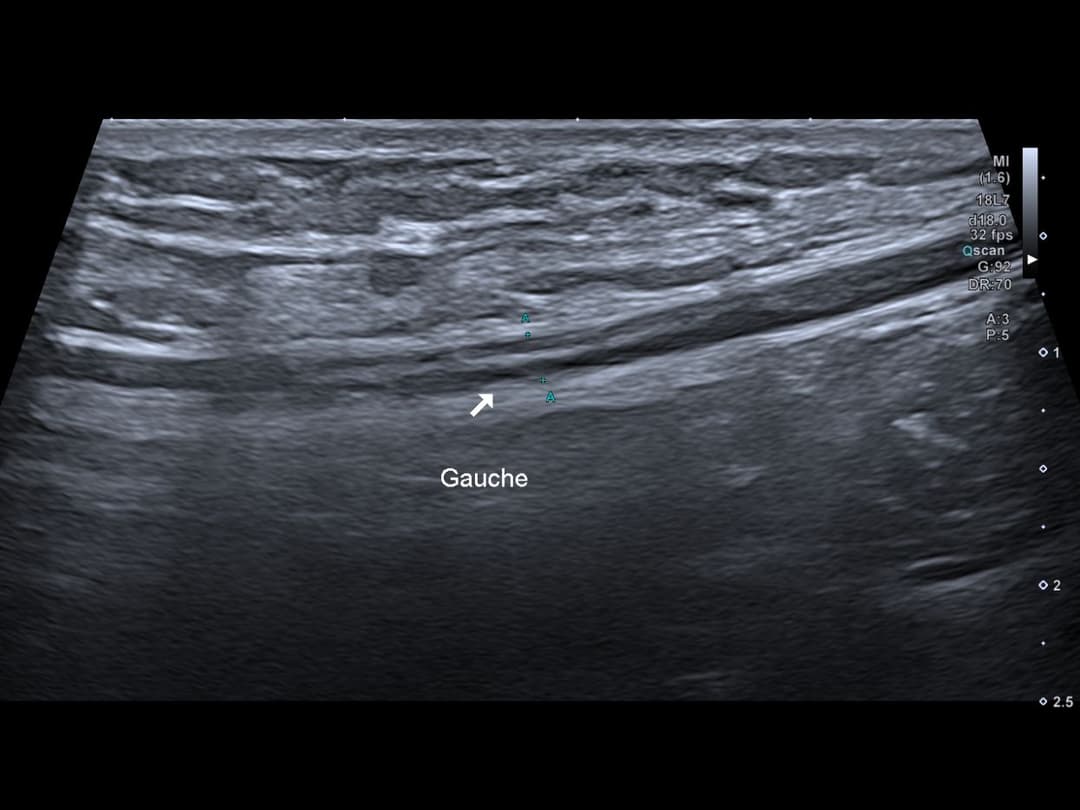

Comparatif de l'aspect continu du NFC de la cuisse gauche

Visualisation du moignon distal du NFC